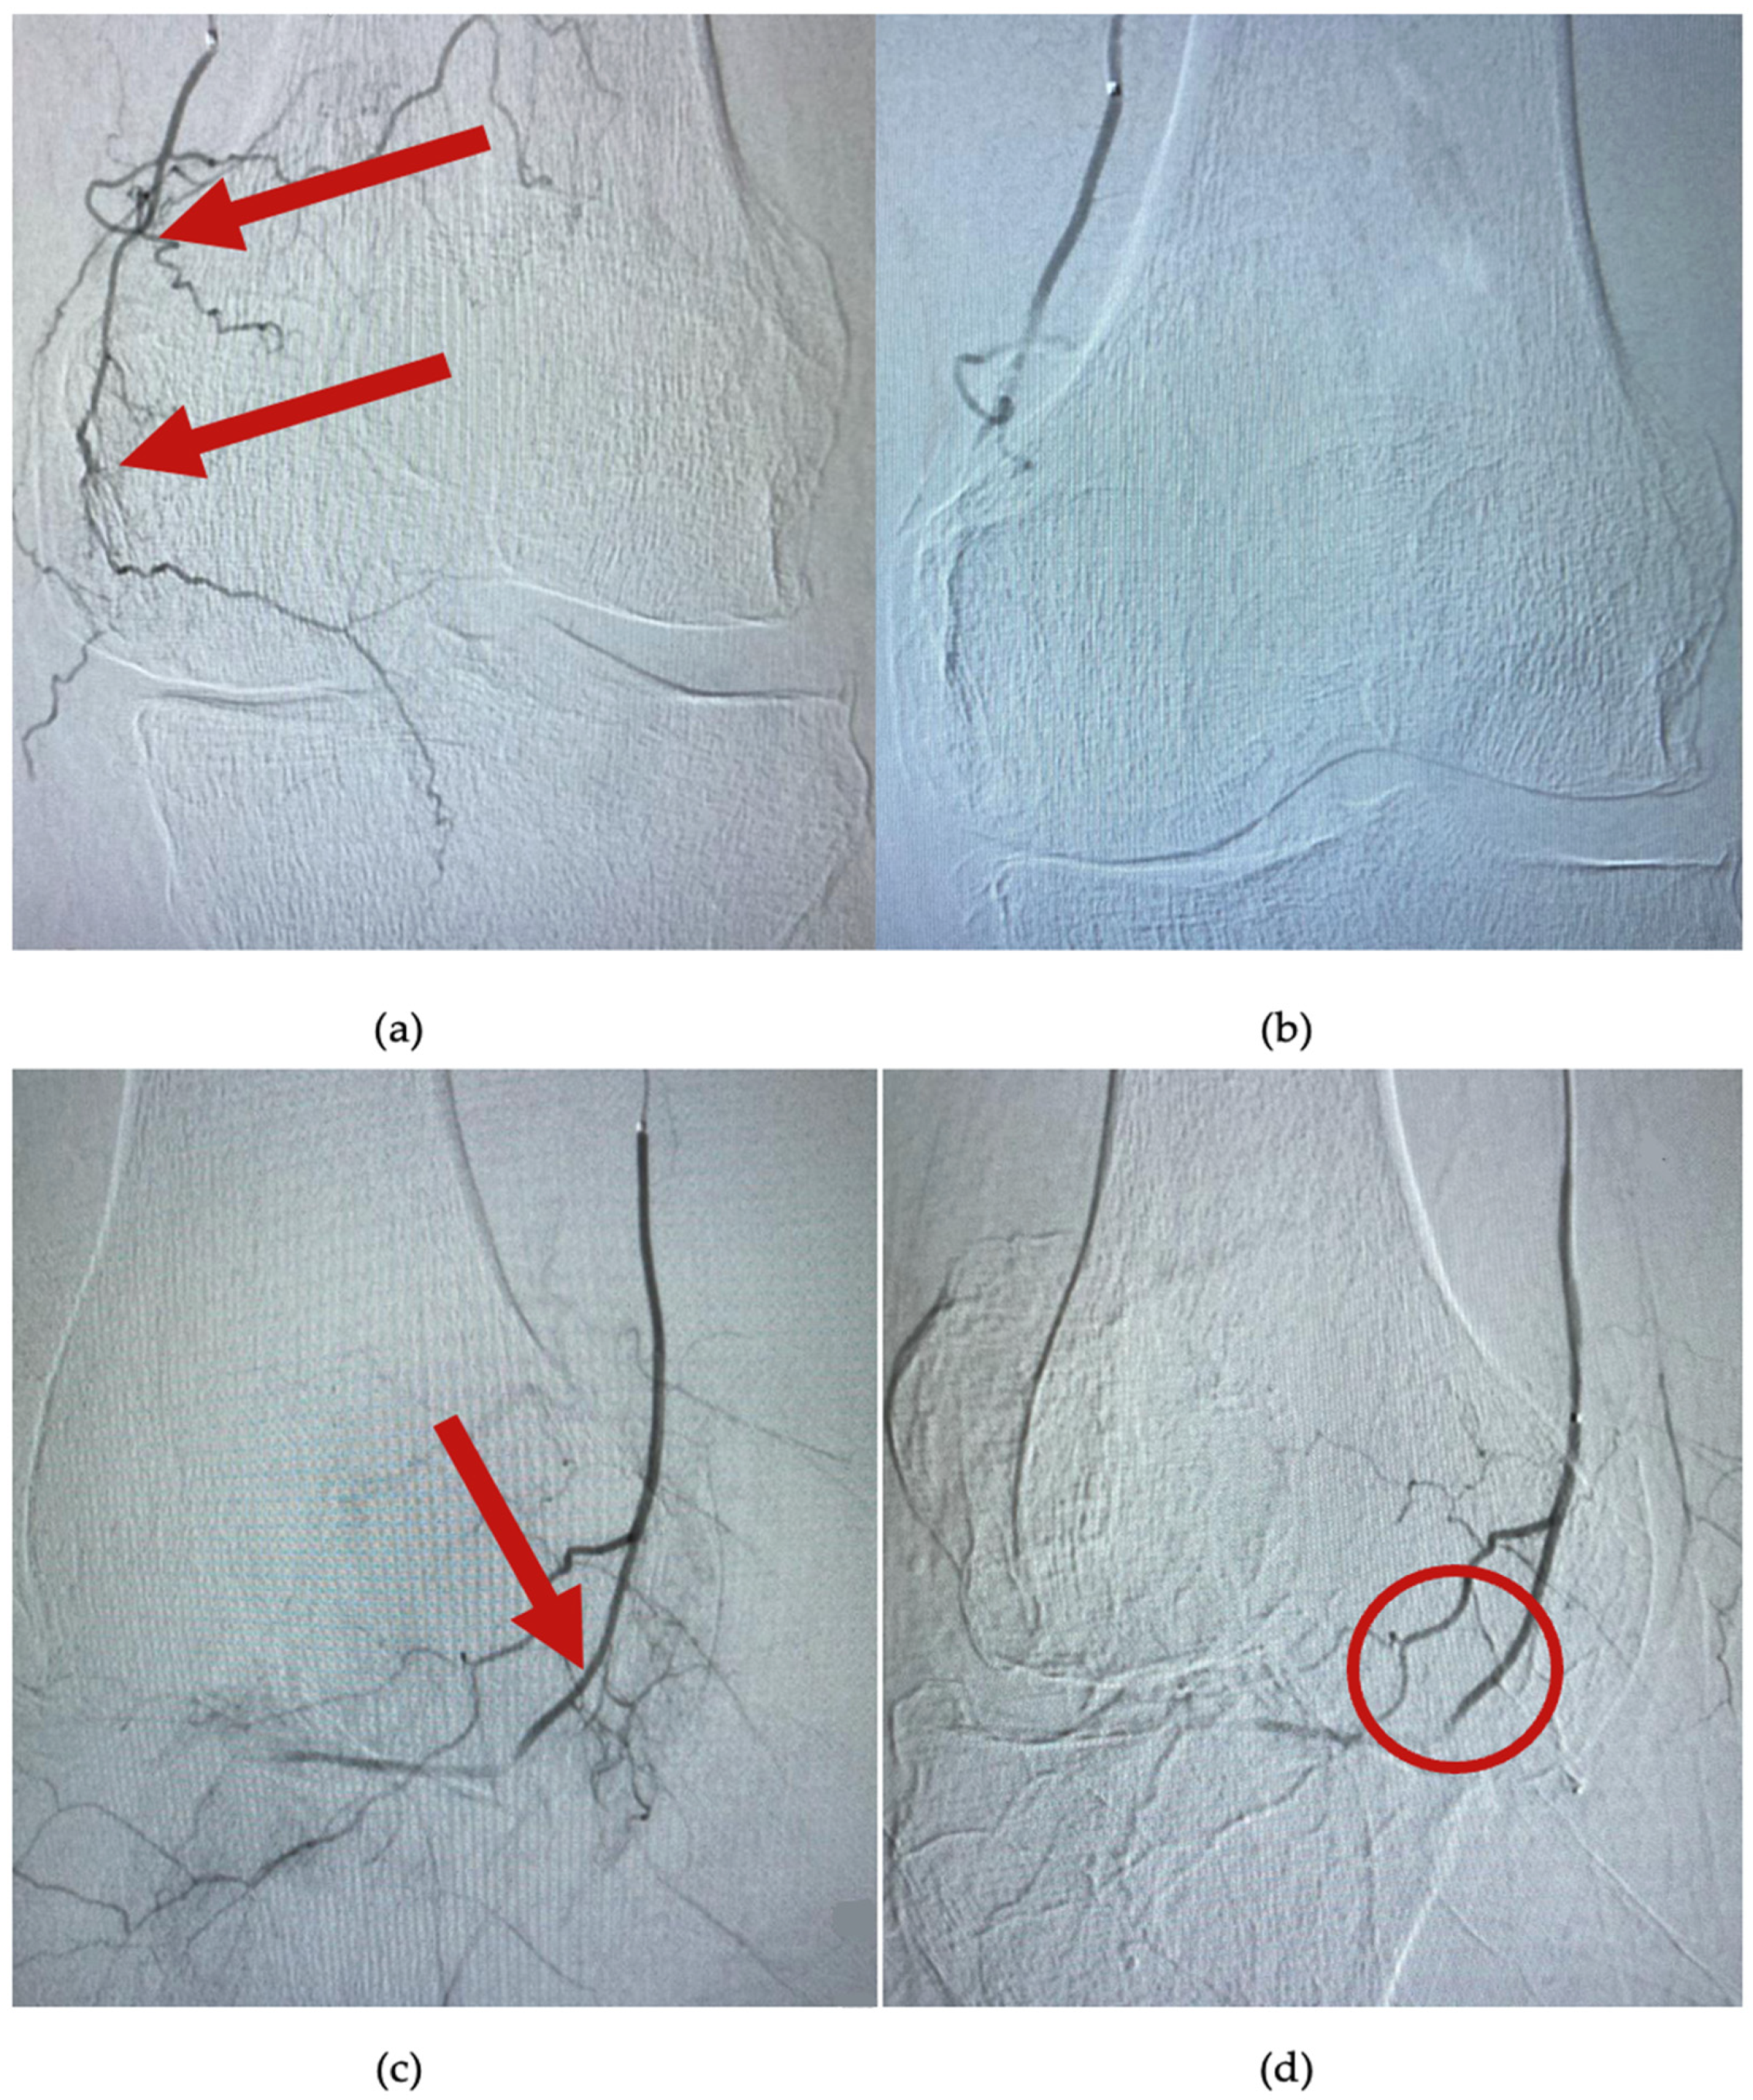

- Okuno, Y.; Korchi, A.M.; Shinjo, T.; Kato, S. Transcatheter arterial embolization as a treatment for medial knee pain in patients with mild to moderate osteoarthritis. Cardiovasc. Interv. Radiol. 2015, 38, 336–343. [Google Scholar] [CrossRef] [PubMed]